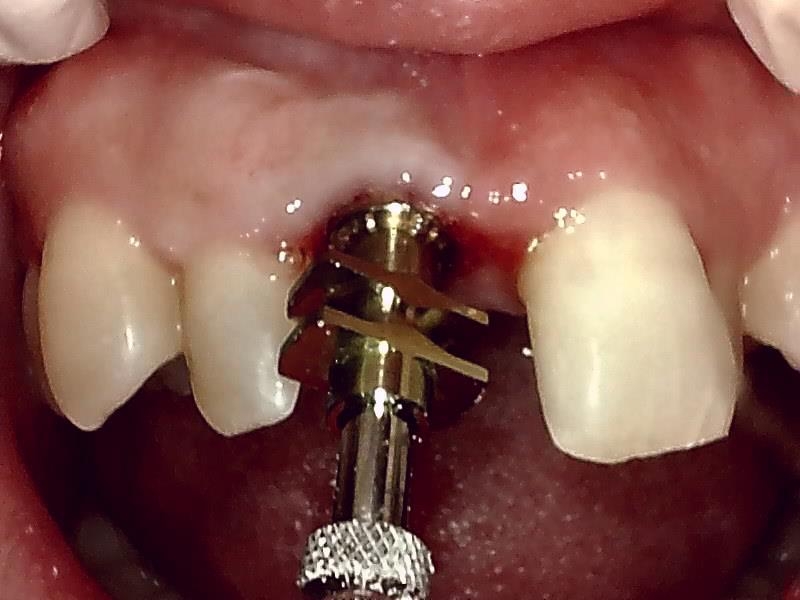

インプラント体の埋入

アバットメントの装着している状況です。

アバットメント装着 (右上)